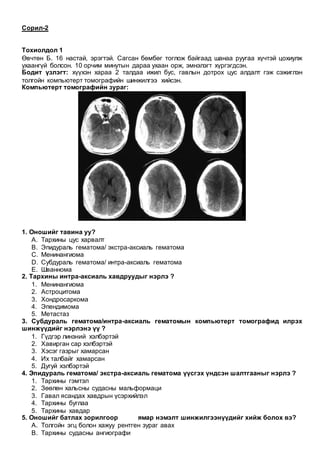

Өвчтөн. H. 68 настай, эрэгтэй турна, ядарч сульдана, хэвлийгээр өвдөнө, өтгөн хатна,

цустай гарна гэсэн зовиуртай эмнэлэгт хандсан.

Бодит үзлэгт: хэвлийн зүүн доод талбайд эмзэглэлтэй, том хэмжээний үүсгэвэр

тэмтрэгдэнэ, цус багадалтын шинжүүд илэрнэ.

Лабораторийн шинжилгээнд: ЦЕШ-Hb-76 анеми, CEA-1107

Ирригограмм:

1.Энэ шинжилгээнд ямар өөрчлөлт илэрсэн бэ?

1. Бүдүүн гэдэсний гауструуд ариласан

2. Бүдүүн гэдэсний уруудах хэсэгт

3. Долихо сигма

4. Алимны голны шинж

5. Дефект